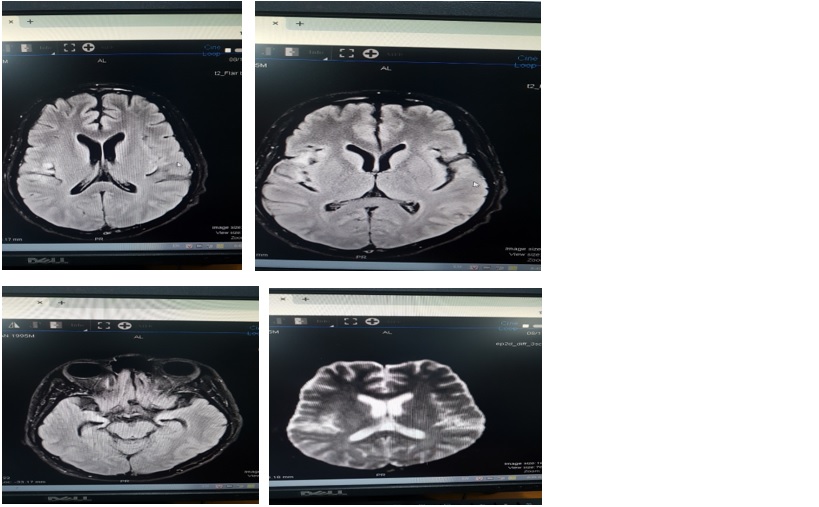

MRI não: tổn thương thùy thái dương